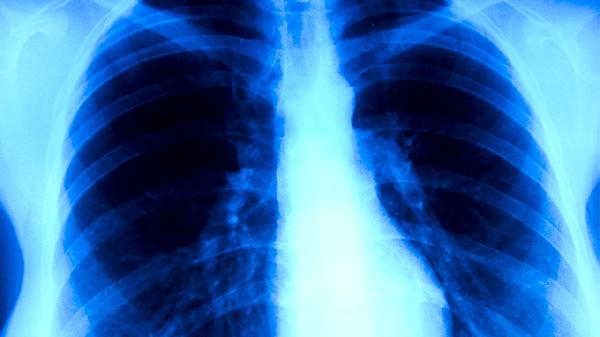

肺结核患者不宜吃的食物

肺结核患者不宜吃辛辣刺激食物、油腻食物、高糖食物、腌制食物以及生冷食物。肺结核是由结核分枝杆菌感染引起的慢性传染病,饮食不当可能加重咳嗽、咳痰等症状或影响药物疗效。

肺结核患者需保证每日优质蛋白摄入,如鸡蛋、鱼肉、豆制品等,促进病灶修复。维生素A、维生素D和锌等营养素有助于增强免疫功能,可适量食用胡萝卜、蘑菇、牡蛎等食物。注意饮食卫生,实行分餐制,餐具定期煮沸消毒。治疗期间严格遵医嘱用药,避免自行调整药物剂量或中断治疗,定期复查胸部影像学和肝肾功能。